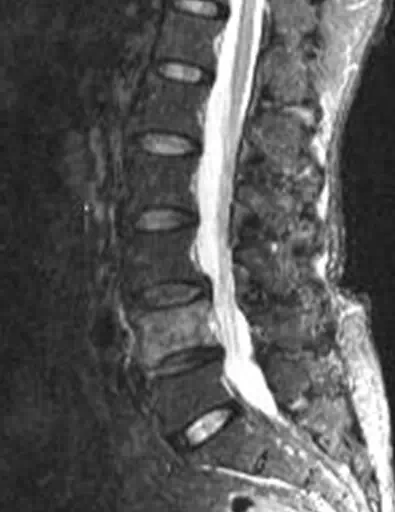

影像学所见:

腰椎:L4椎体及右侧椎弓根骨质破坏。

诊断:骨髓水肿可能由外伤、退变或骨质破坏所致